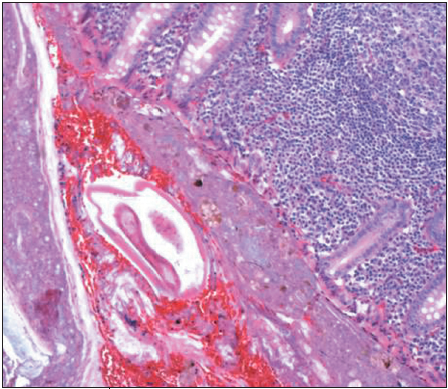

Vasundhara Tolia, MD; Sanjay Khubchandani, MD

A 9-year-old girl was seen in the emergency department (ED) with a 5-day history of non-bilious, non-projectile emesis, decreased appetite, and persistent right lower quadrant pain following an appendectomy...